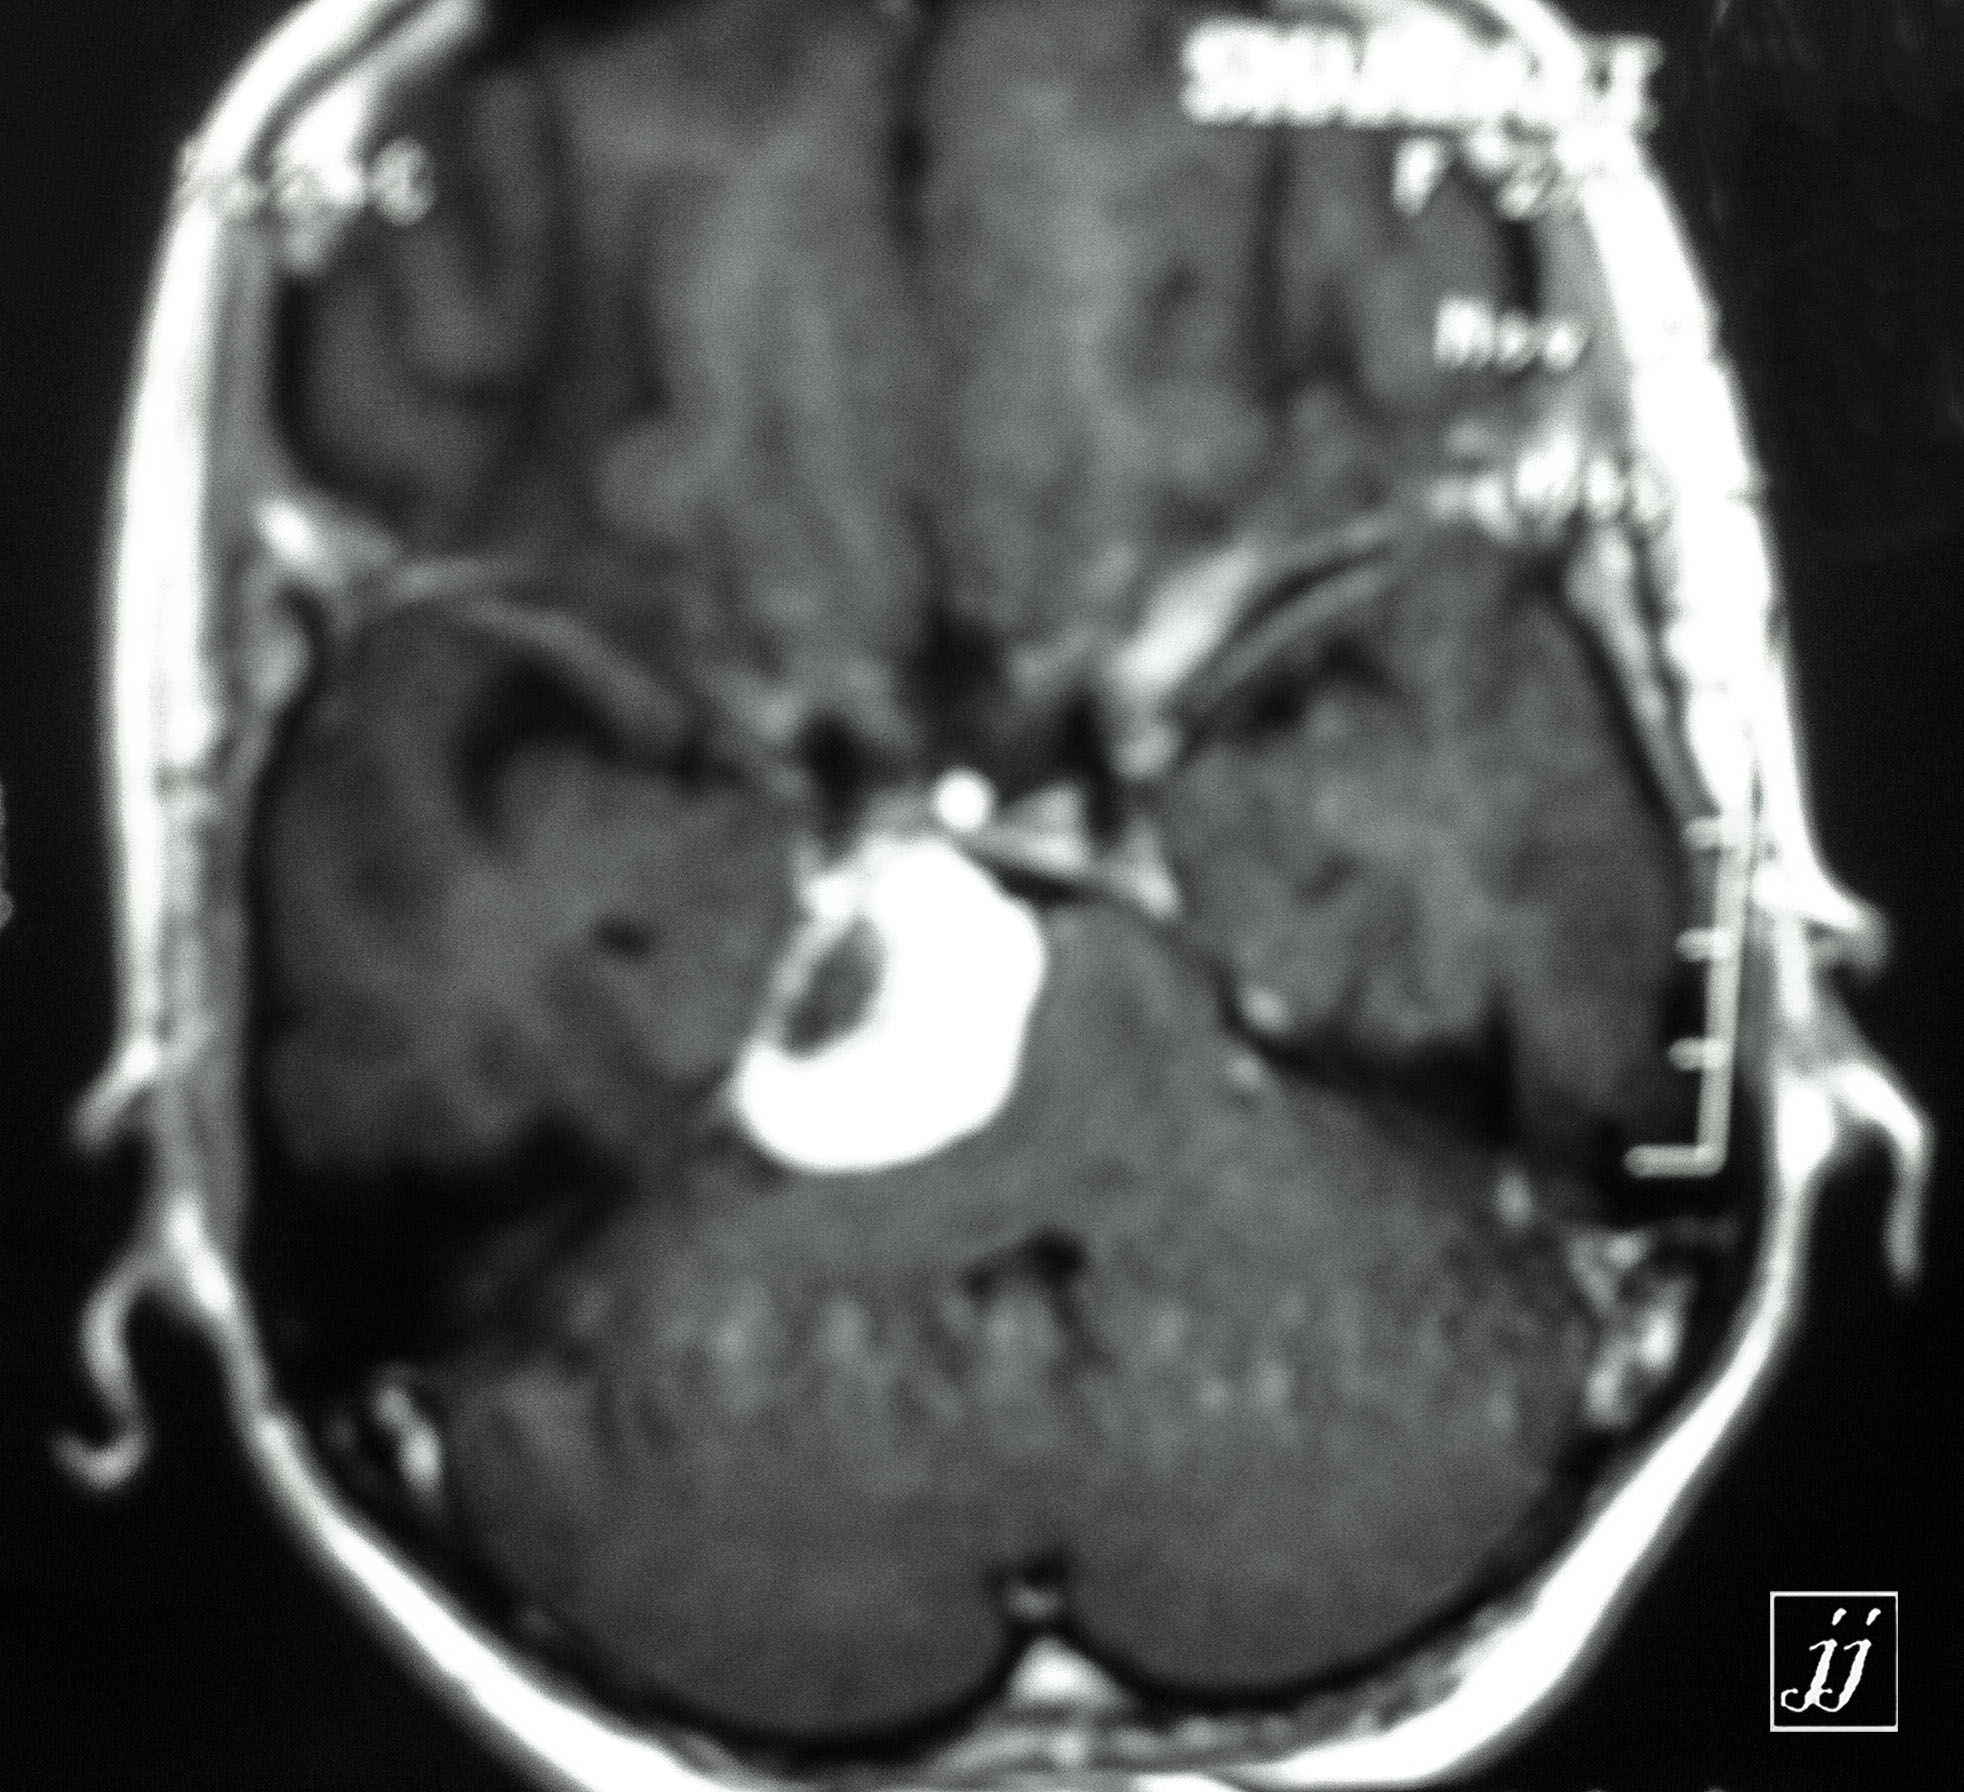

Brain- cystic vestibular schwannoma vs hemangioblastoma (1)